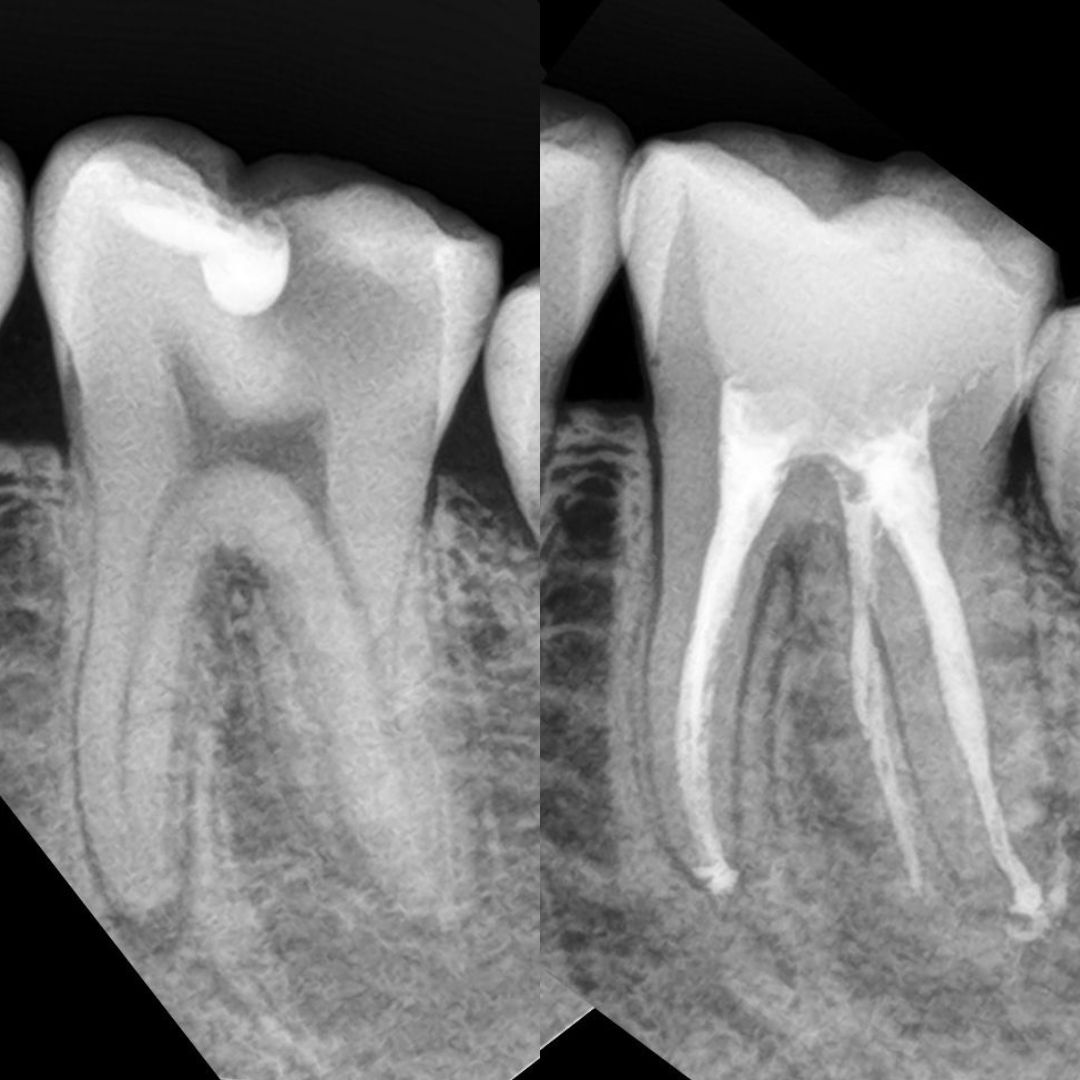

Провели тщательную чистку всех каналов, удалили инфицированные ткани и заполнили каналы лечебным материалом. Через 2 месяца наблюдений зуб полностью запломбировали и восстановили под коронку.